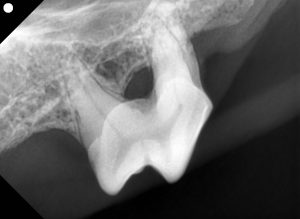

プラークとは、歯の表面に付着する細菌の集合体で、透明または白っぽい粘着性の膜のことです。ご飯やおやつを食べた後、歯に残った食べカスが原因で形成されます。このプラークは、数日放置すると硬化して歯石に変わります。歯石になると通常の歯磨きでは取り除けなくなり、動物病院での処置が必要になります。

プラーク内の細菌が歯茎を刺激し、炎症を引き起こします。進行すると歯肉炎や歯槽膿漏(歯周炎)に発展し、歯が抜けることもあります。 - 全身疾患との関係